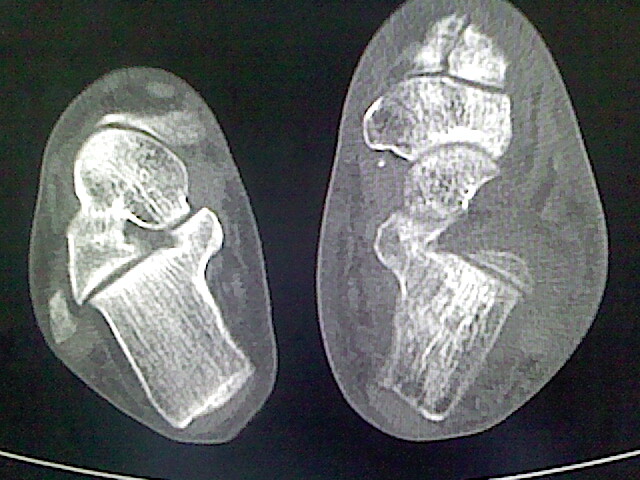

标题: CT16814:男,76岁,左小腿疼痛,不能站立 大家给看看 [打印本页]

男,76岁,左小腿疼痛,不能站立

本例骨质改变主要表现为滑膜或韧带区的骨侵蚀融解(胫腓联合区骨质破坏无硬化边),距骨后部骨质破坏区有硬化边及死骨样改变.所以,本例考虑关节结核可能性大,绒毛膜结节性滑膜炎多发于中年,且极少见于膝髋以外的关节,骨质硬坏也以压陷吸收为主,有明显的硬化边,骨膜增生呈结节状(可以mr鉴别),所以本例暂除外.

另不除外可引起相似表现的其他炎症如布氏杆菌性关节炎等